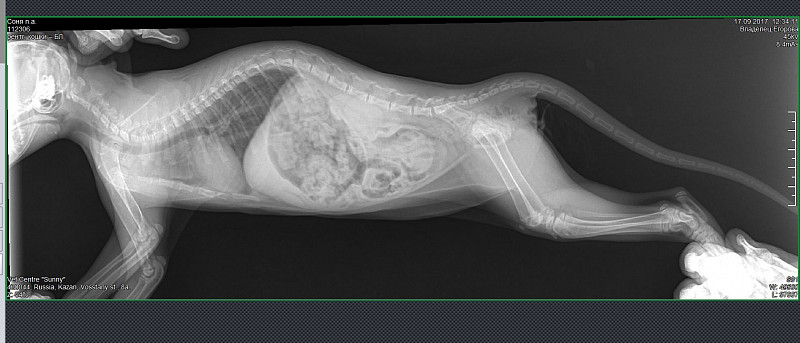

Рентген кошки фото - найдено 30 изображений